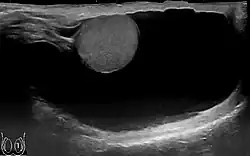

Scrotal ultrasound of a 10 cm large hydrocele testis, with anechoic (dark) fluid surrounding the testicle.

Through diagnostic ultrasound the accumulation of fluids can be diagnosed correctly.